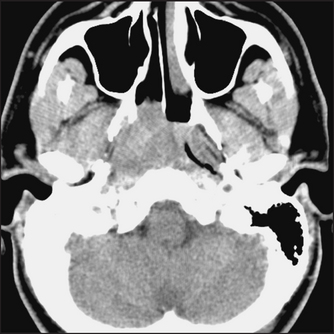

CT scans can be commonly used in the diagnosis of sinusitis and nasopharyngeal tumours. They can help identify the spread of infection into the brain and orbits (see Figures 38.27 and 38.28).

Figure 38.27 Nasopharyngeal carcinoma This CT scan shows a soft-tissue mass obstructing the right nasopharynx and right Eustachian tube. (Haaga. CCT and MRI of the whole body, 5th edn. Mosby, 2008.)